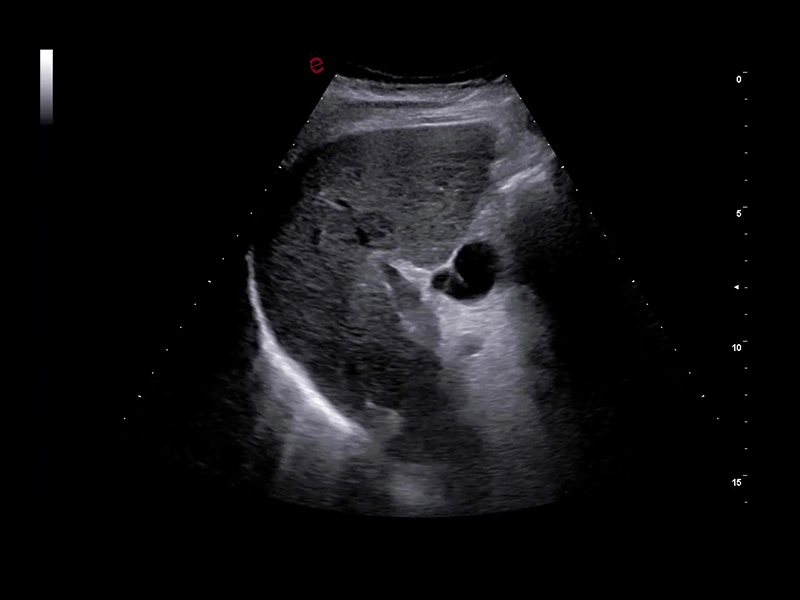

MyLab™C30 - Interventional B-Mode - Kidney

MyLab™C30 - Interventional B-Mode - Kidney